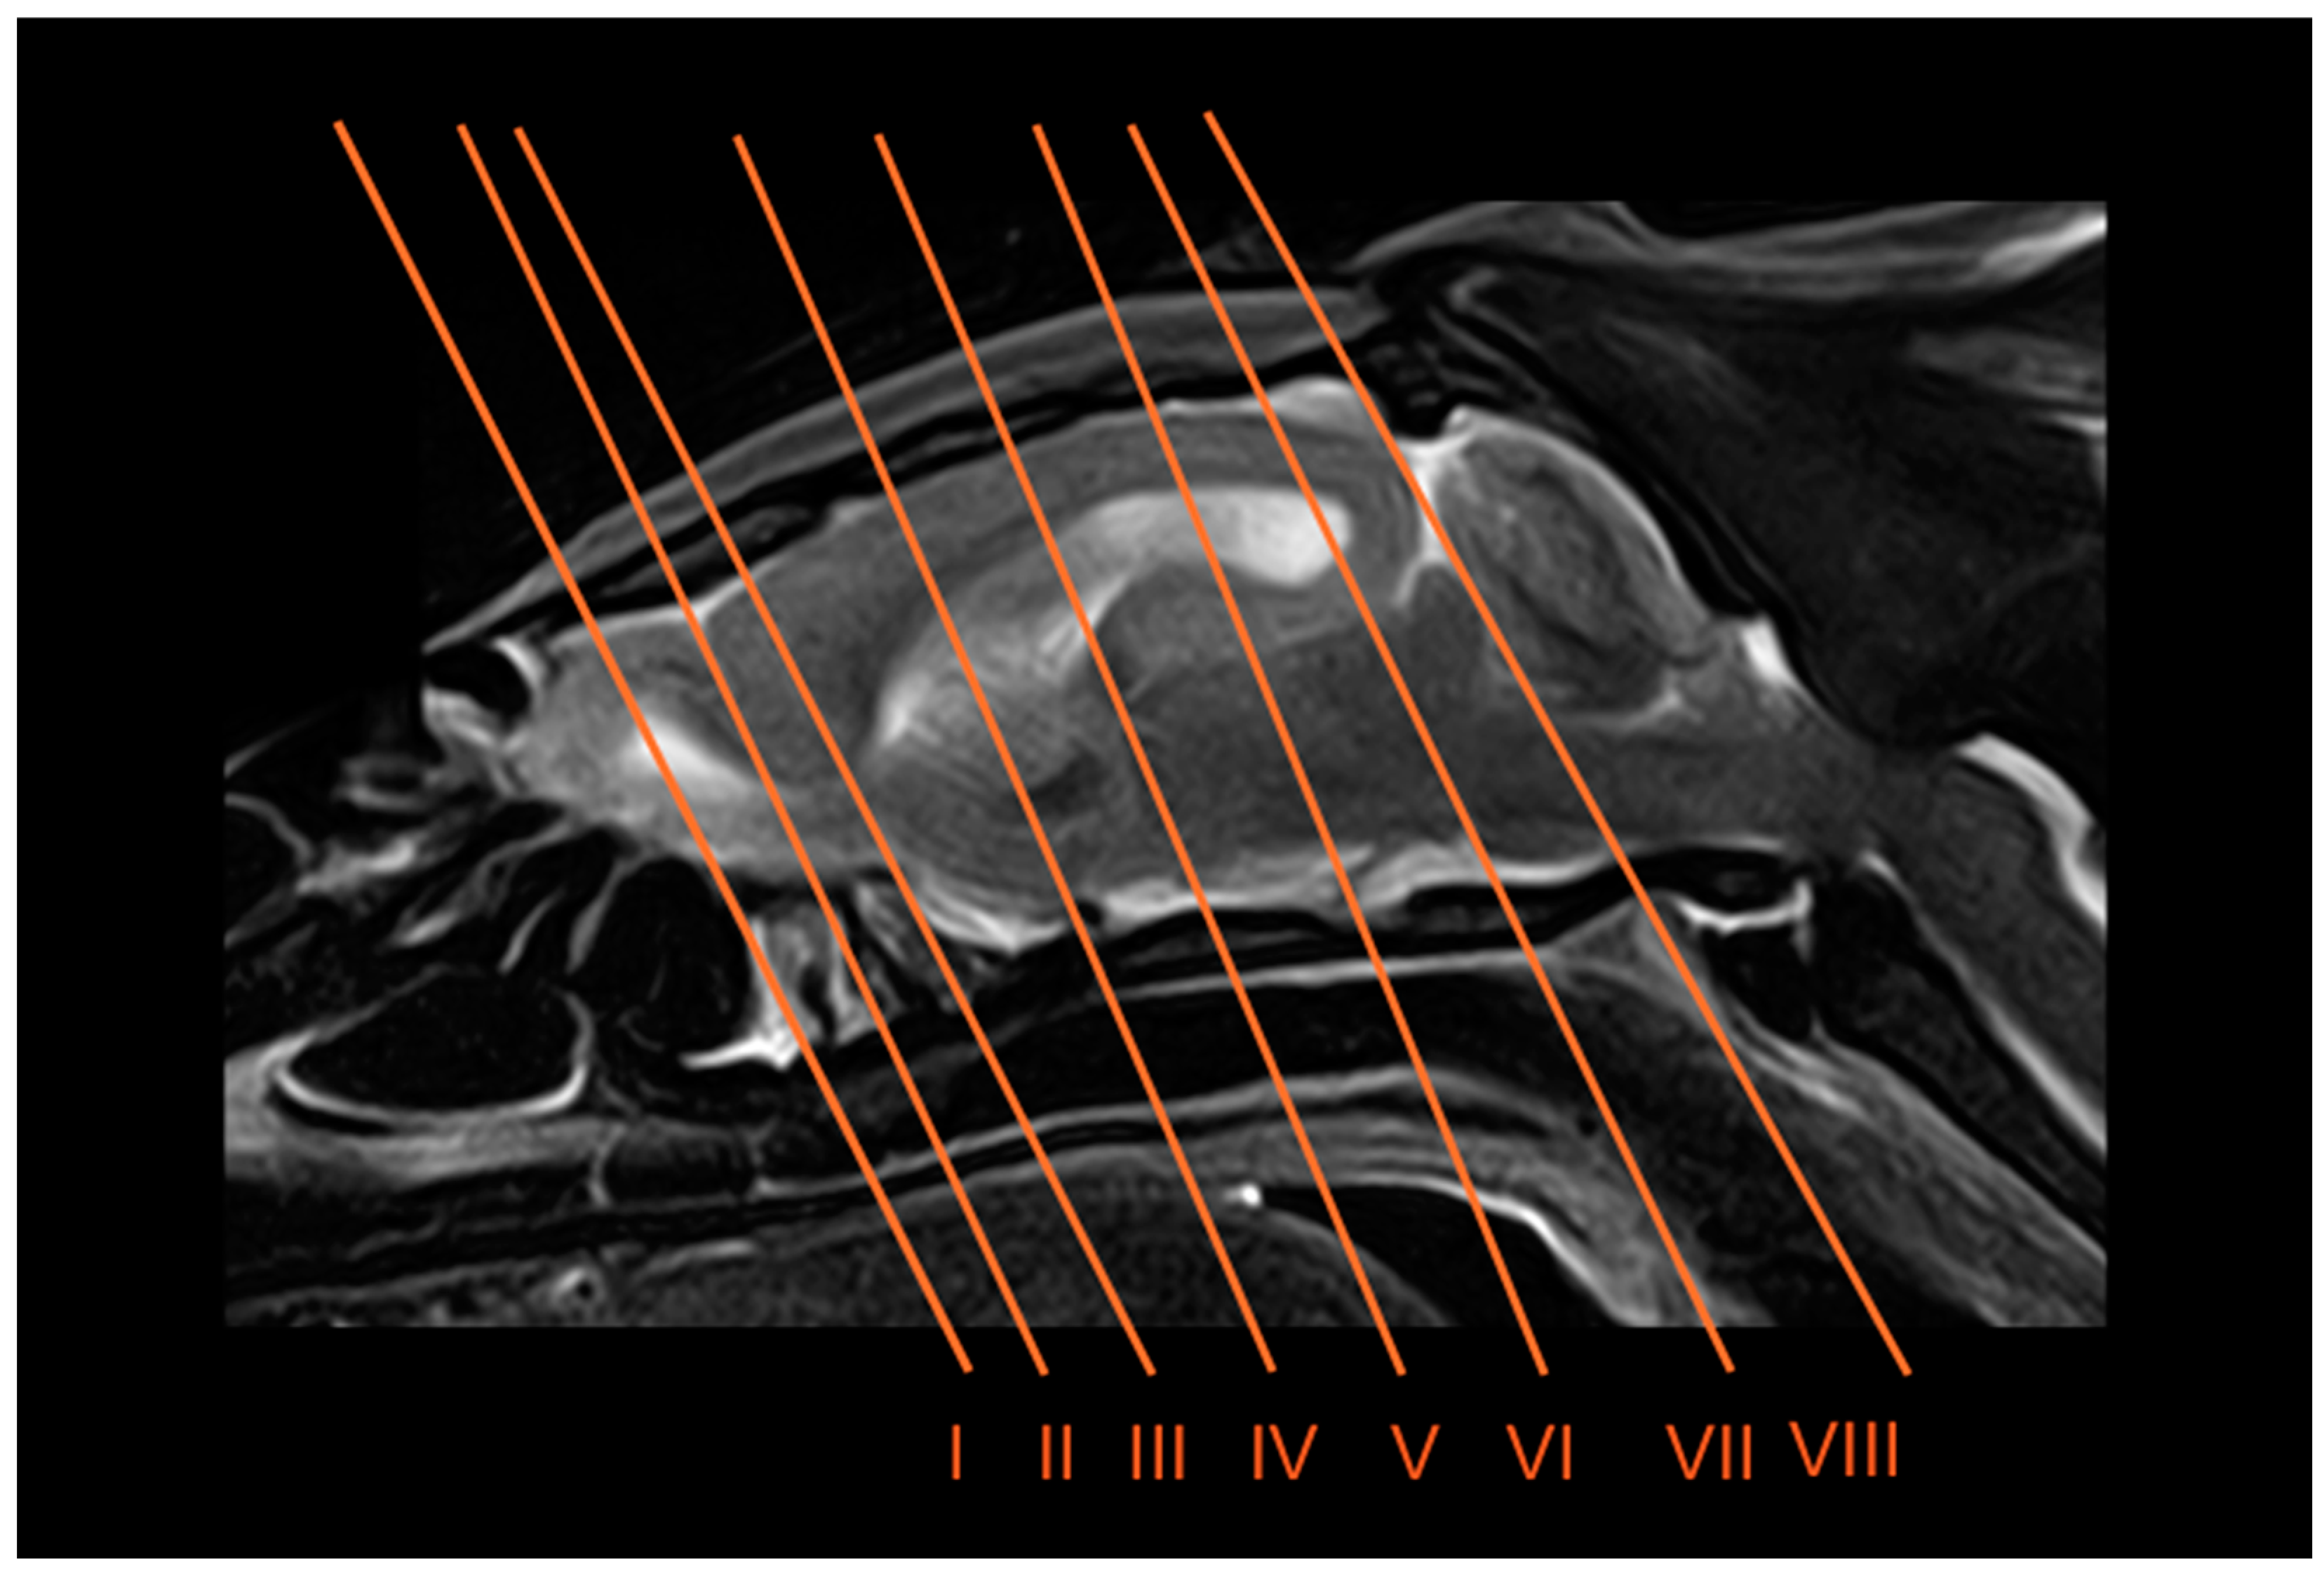

2.4. Anatomical Sections

3.3. Magnetic Resonance Imaging (MRI)